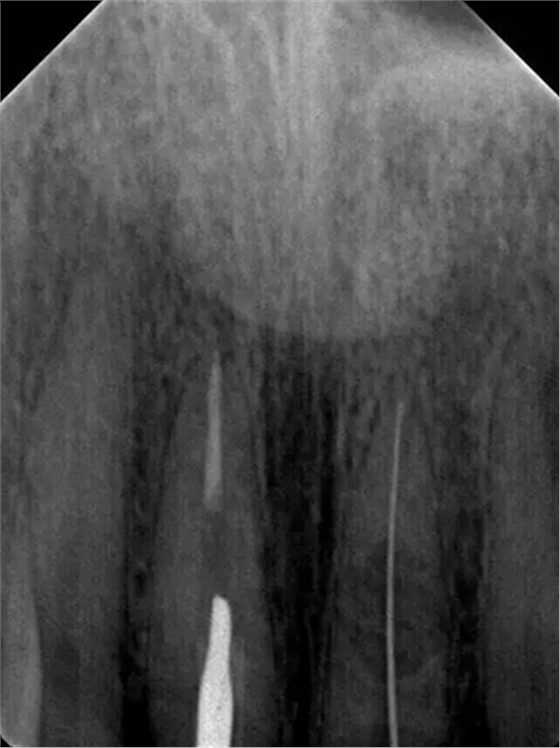

診斷:左上中切牙牙根內(nèi)吸收。治療計劃:左上中切牙根管治療,全冠修復。 治療過程:患者知情同意。使用含1/100,000腎上腺素的4%鹽酸阿替卡因(碧蘭麻,艾龍)局部浸潤麻醉,橡皮障隔濕。去腐未盡露髓,露髓孔出血多。開髓,使用10#不銹鋼K銼(MANI,日本)探查根管,根管中段有鈣化物阻擋,不能達到牙根全長(圖3A)。在顯微鏡下(Leica M400E,萊卡, 德國) 使用超聲尖(E1根管治療超聲尖,啄木鳥公司,中國)通開,采用根管長度測量儀(Root ZX, Morita公司,日本)加診斷絲片法(圖1B)測量根管長22 mm。使用控制扭矩馬達(X-smart,登士柏)和鎳鈦旋轉器械(Hero 642, Micromega)根管預備,根管預備過程中使用5.25%次氯酸鈉溶液沖洗。 根備完成后使用超聲蕩洗根管,5.25%次氯酸鈉溶液3 分鐘, 17% EDTA溶液1分鐘。干燥根管,使用螺旋充填器根管內(nèi)封氫氧化鈣糊,氧化鋅丁香油水門汀暫封。1周后患者復診,患者述無術后不適,檢查暫封完好,無叩痛,不松,牙齦無紅腫瘺管。使用橡皮障隔濕,去除暫封物,超聲蕩洗根管,5.25%次氯酸鈉溶液3 分鐘, 17% EDTA溶液1分鐘。干燥根管,牙膠尖(達雅鼎,中國)和必蘭根充糊劑(Cortisomol, 艾龍公司,法國)熱垂直加壓法根管充填。術后片顯示根充恰填,可見牙膠/糊劑被壓入鈣化物周圍和內(nèi)部縫隙內(nèi)

1月后復查無不適,行全瓷冠修復。8月2周后復查,患者無不適主訴,牙冠美觀,邊緣完好,患牙無叩痛,不松動,牙齦無紅腫瘺管, X線片示根周膜連續(xù),根尖周未見異常。建議患者避免用前牙撕咬食物,定期復查。 討論: 臨床上,由于牙根內(nèi)吸收和牙根外吸收的治療方法和預后不同,常需要對兩者進行鑒別診斷。過去通常采用偏移投照的方法鑒別兩者。在偏移投照片上,外吸收病損和根管輪廓相對位置較正位片會發(fā)生變化,而內(nèi)吸收病損則不會[12]。